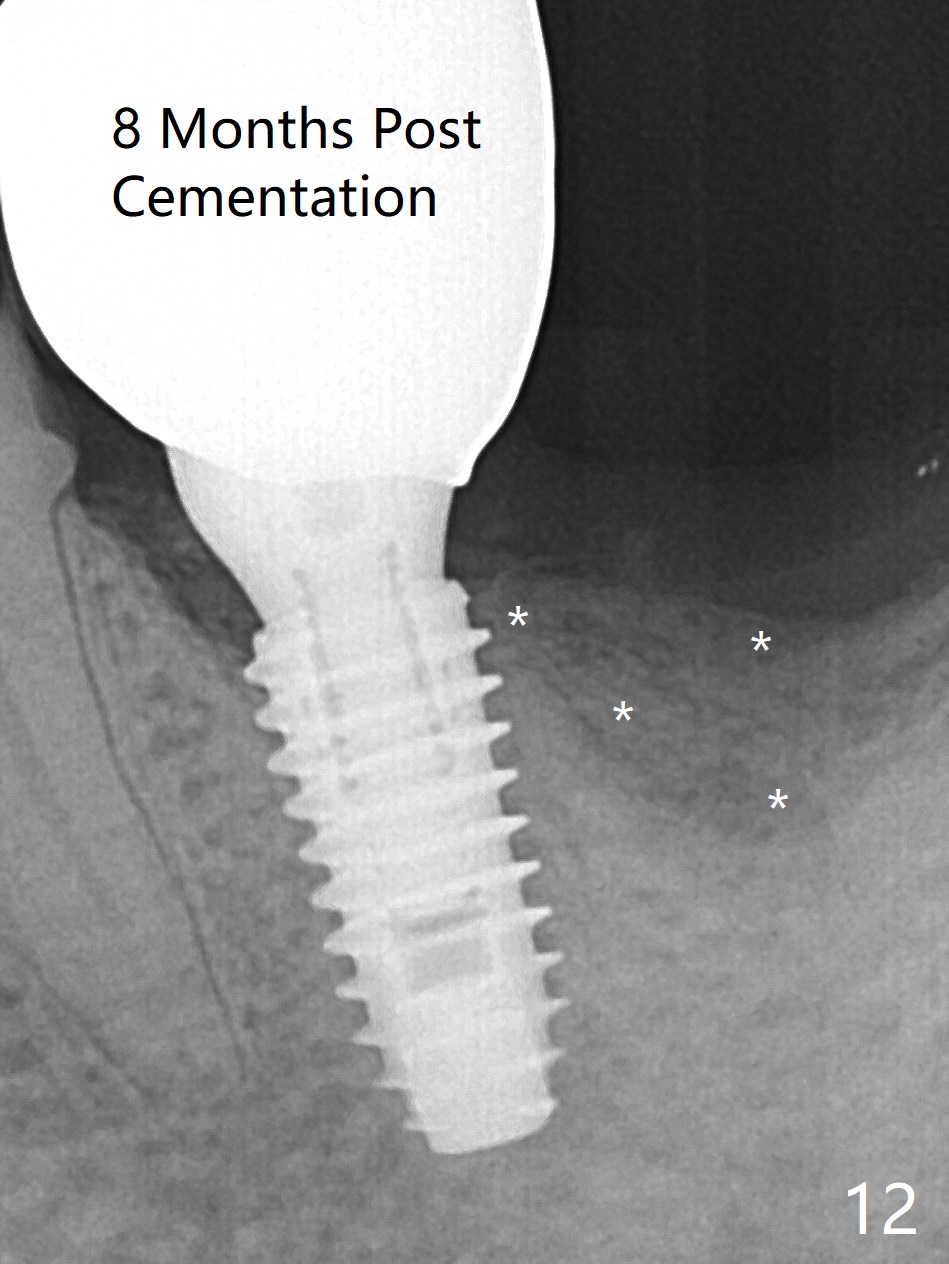

There is shrinkage in the mesial alveolus 1 month postop (Fig.6 *). When the provisional is removed 2 months postop, there is minimal amount of unincorporated bone graft (Fig.7 G) and Osteogen Plug (M, membrane). As the un-attached materials are washed up, the distal socket heals without exposure of implant threads (Fig.8 D). The bone graft settles down and remains in the distal socket 2.5 months postop (immediately pre-cementation, Fig.10 *). The bone graft appears to prevent implant threads from being exposed 2 months post cementation (Fig.11). The bone density in the distal socket increases significantly 8 months post cementation (Fig.12 *).